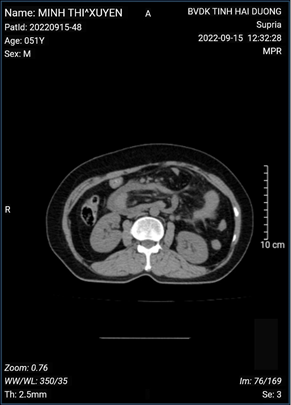

Chụp cắt lớp vi tính ổ bụng: các quai ruột non giãn kèm mức hơi dịch ( hình ảnh tắc ruột)